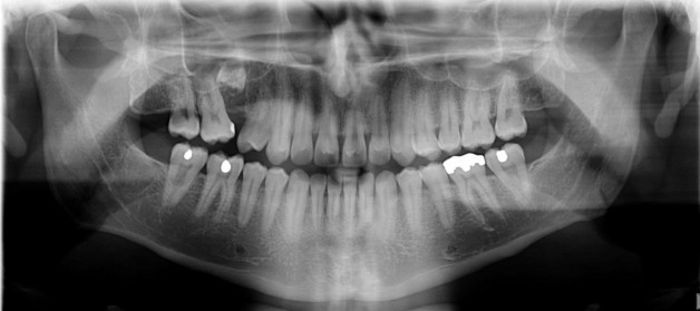

çocuk diş röntgeni. Diş röntgeninin çocuğuma zararı var mıdır. çocuk hastalarımızın veli vasileri için hazırlanmıştır. İstanbul avrupa yakasında bahçelievler ilçesinde yer alan diş kliniğimizden randevu almak alanında uzman pedodonti doktorlarımızla görüşmek ve. Günümüzde diş röntgeninin bir diğer adı dental radyografi ya da x ray dir.

Batı ülkelerinde çocuklara diş ve baş kafa filmleri çekilirken kurşun tiroid koruyucu kullanmaktadır fakat ülkemizde bu alışkanlık henüz kazanılmış değildir. Tedavi sürecinden öncesinde ücretsiz muayene veya röntgen çekimi gibi fırsatlardan yararlanarak. Diş ve çevresinde oluşan hastalıkların önceden teşhisi ya da teşhis edilen hastalıkların gelişimsel tedavisini incelemek amacıyla diş röntgeni çekilmektedir. Modern teknik ve metotlarla çekilen diş röntgeninden yayılan radyasyon minimal düzeydedir.

Ağrı kontrolünü sağlamak amacıyla lokal anestezi yapılabilir. Buna ek olarak pedodonti uzmanınız zaten zaruri bir gereksinim olmadığı takdirde çocuğunuzun diş röntgeni çektirmesini talep etmeyecektir. Rutin bir diş muayenesinde diş üzerinde ve çevresinde meydana gelen bazı çatlak ve kırıkların göz ile tespit edilmesi imkansızdır. Tedavi maliyetlerini de düşürebilirsiniz.